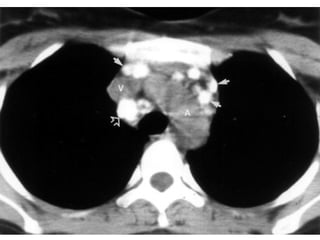

5. Subaortic LNs

(aortopulmonary window LNs)

6. para-aortic LNs

• Anterior & lateral to the ascending thoracic

aorta & aortic arch.

7. Subcarinal LNs

• Upper border: carina of the trachea.

• Lower border: bronchus intermedius on

the right and left lower lobe bronchus on

the left.